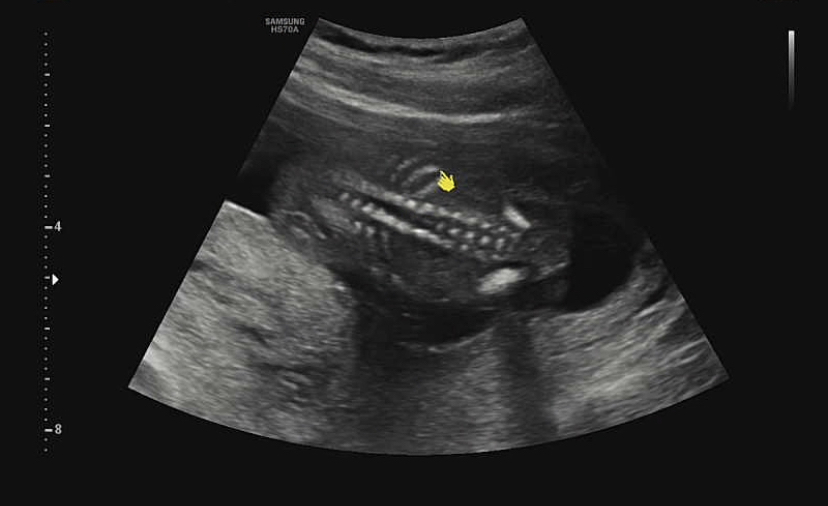

16주가 되면 아기가 꽤 커서 한 초음파 화면에 잡히지 않는다. 그래서 머리-몸통-발처럼 한 군데씩 돌면서 초음파를 봤다.

그리고 귀여운 허벅지 공개! 허벅지뼈가 보였어. 허벅지 뼈 길이도 아이의 성장에 중요한 요소인지 길이를 꼼꼼히 재줬다.